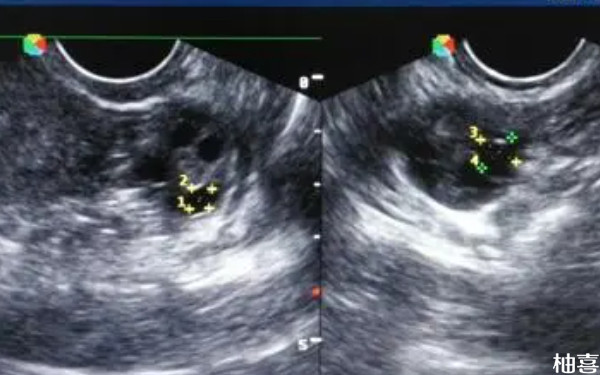

试管促排10天内膜18了正常吗?

女性患者在试管促排10天后内膜厚度达到了18一般是不正常的,建议患者前往人类辅助生殖机构进行身体检查,明确具体情况,并做针对性治疗,而在此期间,病人需要注意营养均衡,多吃富含蛋白质、维他命、矿物质的食物,避免食用辛辣刺激性食物,同时还要保持良好的心态,不要过于紧张和焦虑。